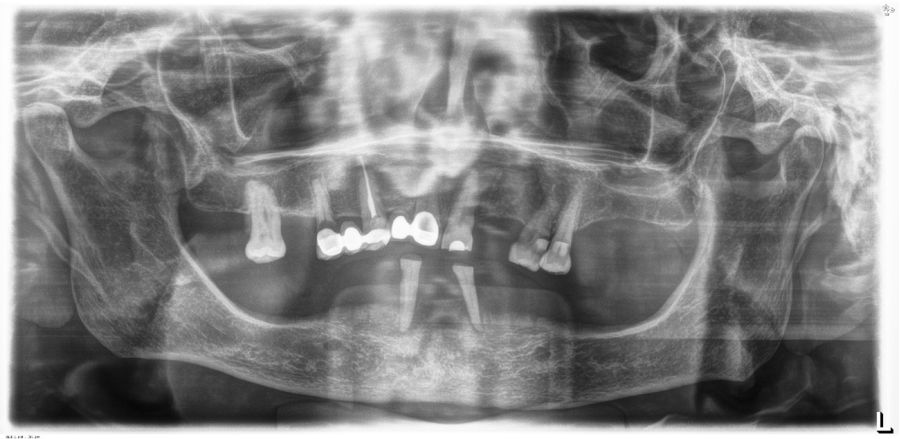

El análisis global de los 99 implantes reveló una pérdida ósea marginal media de 0,77 ± 0,26 mm en la superficie mesial y 0,79 ± 0,29 mm en la distal, valores que se mantuvieron dentro de los rangos considerados clínicamente aceptables para rehabilitaciones mandibulares. Cuando los implantes se categorizaron según su longitud, se observaron diferencias claras entre ambos grupos. Los implantes cortos (<10 mm) mostraron una pérdida ósea mesial media de 0,61 ± 0,23 mm y distal de 0,56 ± 0,22 mm, mientras que los implantes largos (≥10 mm) presentaron pérdidas significativamente mayores (mesial: 0,92 ± 0,19 mm; distal: 0,99 ± 0,17 mm). Dado que las pruebas de normalidad (Shapiro–Wilk) mostraron una distribución no normal en todos los grupos (p < 0,001), se aplicó la prueba no paramétrica de Mann–Whitney U. Los resultados confirmaron diferencias estadísticamente significativas tanto en la pérdida ósea mesial (U = 2068,5; p < 0,001) como en la distal (U = 2247,0; p < 0,005), indicando que los implantes cortos presentaron un comportamiento óseo más favorable que los implantes largos a lo largo del tiempo. Durante el tiempo de seguimiento que fue de media de 12,2 años (+/- 4,4; rango 6-23 años) no se objetivaron fracasos en ninguno de los implantes por lo que la supervivencia acumulada fue del 100%. El análisis del periodo de seguimiento mostró diferencias claras entre ambos grupos. Los implantes largos (≥10 mm) presentaron un tiempo medio de función de 14,1 ± 4,2 años (rango: 9–23 años), mientras que los implantes cortos (<10 mm) registraron un seguimiento significativamente menor, con una media de 9,8 ± 2,7 años (rango: 6–15 años). En las Figuras 3- 10 se muestran dos casos incluidos en el estudio, uno de cada situación descrita.

Un aspecto clave para interpretar estos resultados es el tiempo de seguimiento, ya que en nuestra cohorte los implantes largos presentaron significativamente más años en función intraoral. El análisis del periodo de seguimiento mostró diferencias claras entre ambos grupos. Los implantes largos (≥10 mm) presentaron un tiempo medio de función de 14,1 ± 4,2 años (rango: 9–23 años), mientras que los implantes cortos (<10 mm) registraron un seguimiento significativamente menor, con una media de 9,8 ± 2,7 años (rango: 6–15 años). La comparación mediante la prueba de Mann–Whitney U reveló diferencias estadísticamente significativas entre ambos grupos (p < 0,001). Este mayor tiempo en función de los implantes largos constituye un factor relevante a considerar en la interpretación de las diferencias observadas en la pérdida ósea marginal. La literatura demuestra que la pérdida ósea crestal es más pronunciada durante los primeros 12 meses y tiende a estabilizarse posteriormente, aunque existe un remodelado lento y continuo asociado al tiempo 36,48–50. Por tanto, es plausible que parte de la mayor pérdida ósea observada en los implantes largos esté relacionada con el mayor periodo de observación, aunque con los datos y el análisis realizado en el presente estudio, no podemos establecer esta correlación. Este factor debe considerarse al comparar ambos grupos y será analizado en estudios futuros con modelos de regresión ajustados por tiempo.

Por otro lado, la ausencia de fracasos implantares en ambos grupos es especialmente destacable, ya que la rehabilitación completa sobre cuatro implantes ha sido históricamente objeto de preocupación biomecánica, tanto por la carga concentrada como por la presencia potencial de cantilevers en las prótesis12,15. En técnicas como el All-on-4 descrito por Malo, donde los implantes distales se angulan 30–45°, se han reportado supervivencias elevadas, pero también mayores tasas de complicaciones mecánicas y protésicas, especialmente relacionadas con la sobrecarga distal y la fatiga del tornillo o de la estructura13,47. En contraste, la estrategia utilizada en este estudio, basada en cuatro implantes paralelos, cortos o largos según la disponibilidad ósea, reduce la complejidad biomecánica y distribuye las cargas de forma más homogénea, minimizando los momentos de flexión sobre los implantes distales18. La capacidad de los implantes cortos para sostener rehabilitaciones completas ha sido respaldada por múltiples estudios. Diferentes trabajos de la literatura internacional han demostrado que los implantes cortos (≤8 mm) alcanzan supervivencias comparables a los convencionales y presentan tasas similares de complicaciones mecánicas, siempre que se respeten principios biomecánicos como la ferulización rígida, la correcta pasividad protésica y la ausencia de cantilevers excesivos21,22,35–41,51–56. Los resultados de este estudio refuerzan esta evidencia, mostrando que los implantes cortos no solo no incrementan la pérdida ósea, sino que pueden presentar un comportamiento marginal más estable en el largo plazo.

En relación con el voladizo, en nuestra cohorte únicamente las prótesis soportadas por implantes largos presentaban un mayor cantilever distal, mientras que las rehabilitaciones basadas en implantes cortos no lo requerían o tenían uno de longitud mínima. La literatura indica que la presencia de cantilever puede aumentar de forma significativa las tensiones sobre los implantes distales y favorecer el remodelado óseo marginal12,15,57–60. Este hecho podría contribuir a explicar las mayores pérdidas óseas del grupo de implantes largos, al margen del dato del tiempo de seguimiento anteriormente discutido y subraya la relevancia clínica de planificar rehabilitaciones sin voladizo siempre que la anatomía y los implantes cortos lo permitan. Finalmente, la estabilidad de las rehabilitaciones en ambos grupos confirma que el protocolo estandarizado aplicado en esta serie constituido por fresado biológico, carga progresiva y estructura híbrida atornillada sobre transepitelial, con implantes siempre paralelos, sin inclinaciones distales, proporciona un entorno favorable para la osteointegración y el mantenimiento periimplantario a largo plazo. Este enfoque coincide con las tendencias actuales hacia tratamientos mínimamente invasivos, pero biomecánicamente sólidos, reduciendo la necesidad de angulaciones extremas o regeneraciones complejas sin comprometer los resultados clínicos30,32,61,62.